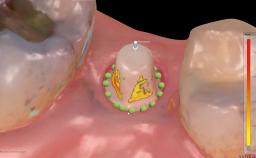

Leon Pariente and Karim Dada outline the Immediate Implant Placement and Restoration of a Maxillary Left Central Incisor with a Provisional Crown, demonstrating how the hard and soft tissue architecture can be maintained with a Type 1A treatment protocol and a fixed provisional, providing an esthetic and comfortable immediate solution.

A 34-year-old female patient with high esthetic expectations, a non-smoker with no relevant medical history (ASA class 1), was referred to the practice for replacement of her failing maxillary left central incisor (tooth 21), which exhibited a vertical root fracture as diagnosed by the referring endodontist under the microscope. This case illustrates a type 1A treatment protocol (Gallucci and coworkers 2018) complete with diagnosis, treatment decisions, and clinical and laboratory steps.

| Timing of placement | Immediate Placement (extraction sockets) (Type I) |

| Available apical bone to achieve primary stability | Sufficient height ( ≥ 4 mm) and width (> 2 mm around apex of planned implant) |

| Socket walls | Intact |

| Thickness of buccal wall | 2mm or greater |

| Anticipated residual defect after implant placement | 2 mm or less |